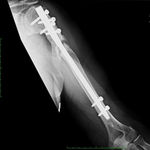

She was advised of the need to do some sort of stabilization which is necessary since the use of low-dose ultrasound has not helped in the healing process. She was unwilling to have any further operative intervention and sought further options. Eventually, she agreed to a fourth procedure of intra-medullary nail stabilization of the fracture and had this carried out in April 2011. An intramedullary nail was inserted in an antegrade manner and she has since gone on to heal the fracture site completely and has regained most of the function of the upper limb with no pain.